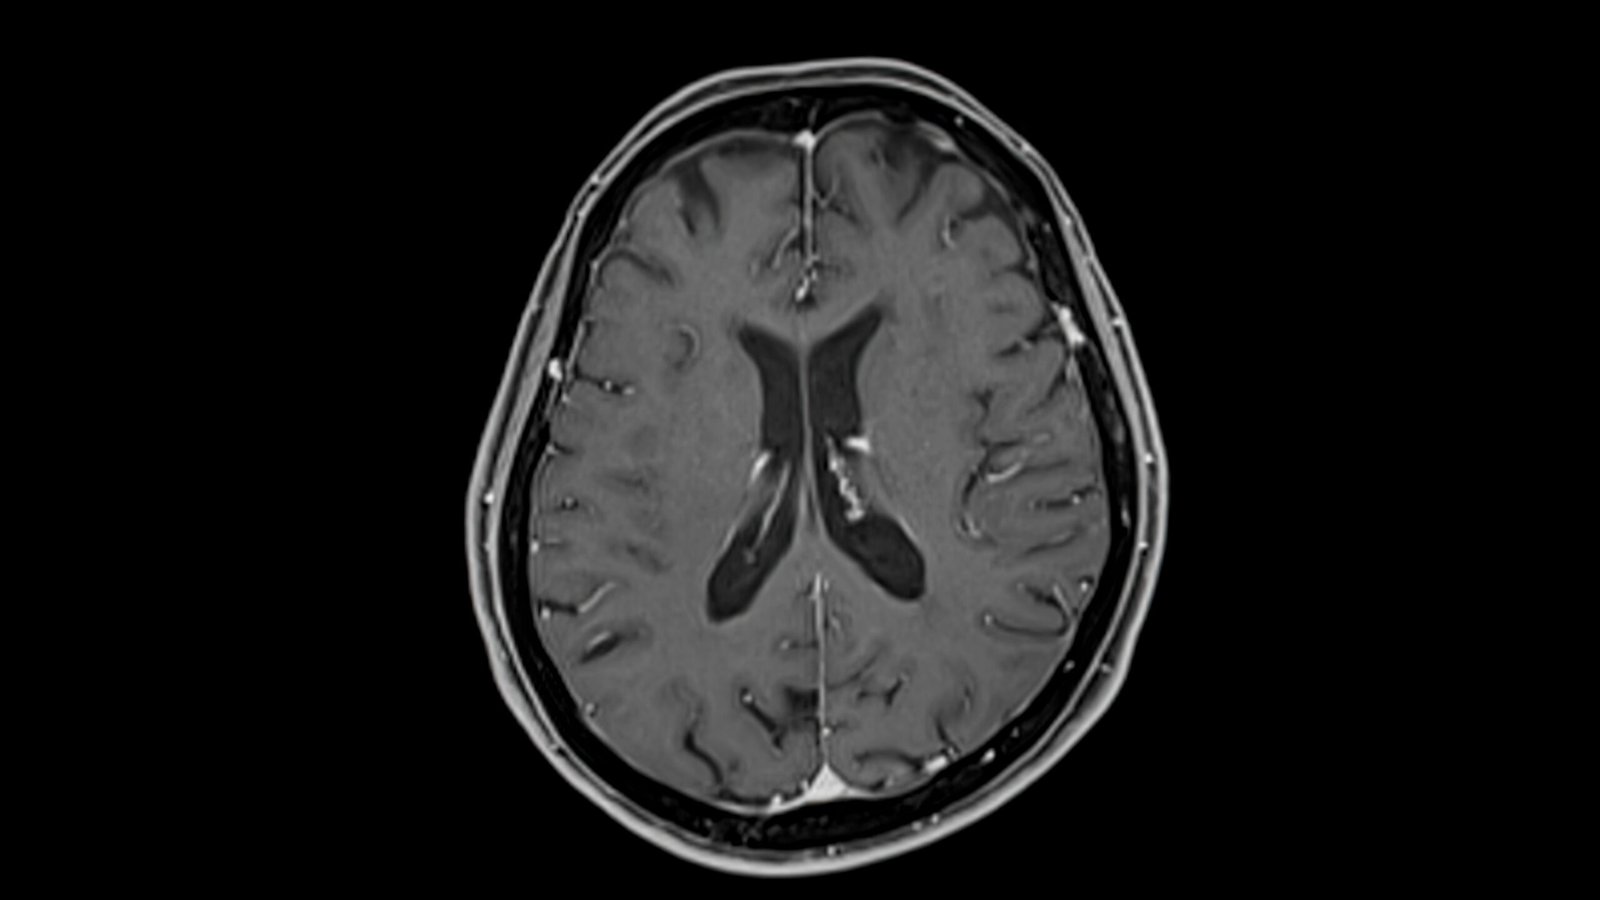

Understanding the Science: Alpha-Synuclein Dysfunction

At the biological level, MSA is thought to be driven by the dysfunction of alpha-synuclein, a protein that normally plays a role in neuronal function. In MSA, this protein misfolds, aggregates, and accumulates within cells — particularly in oligodendrocytes — forming toxic clumps known as glial cytoplasmic inclusions.

Dr. Barbuti compares the process to “a ball of elastic bands that has lost its structure and usefulness.” Once misfolded, the protein becomes difficult for the brain to break down or recycle.